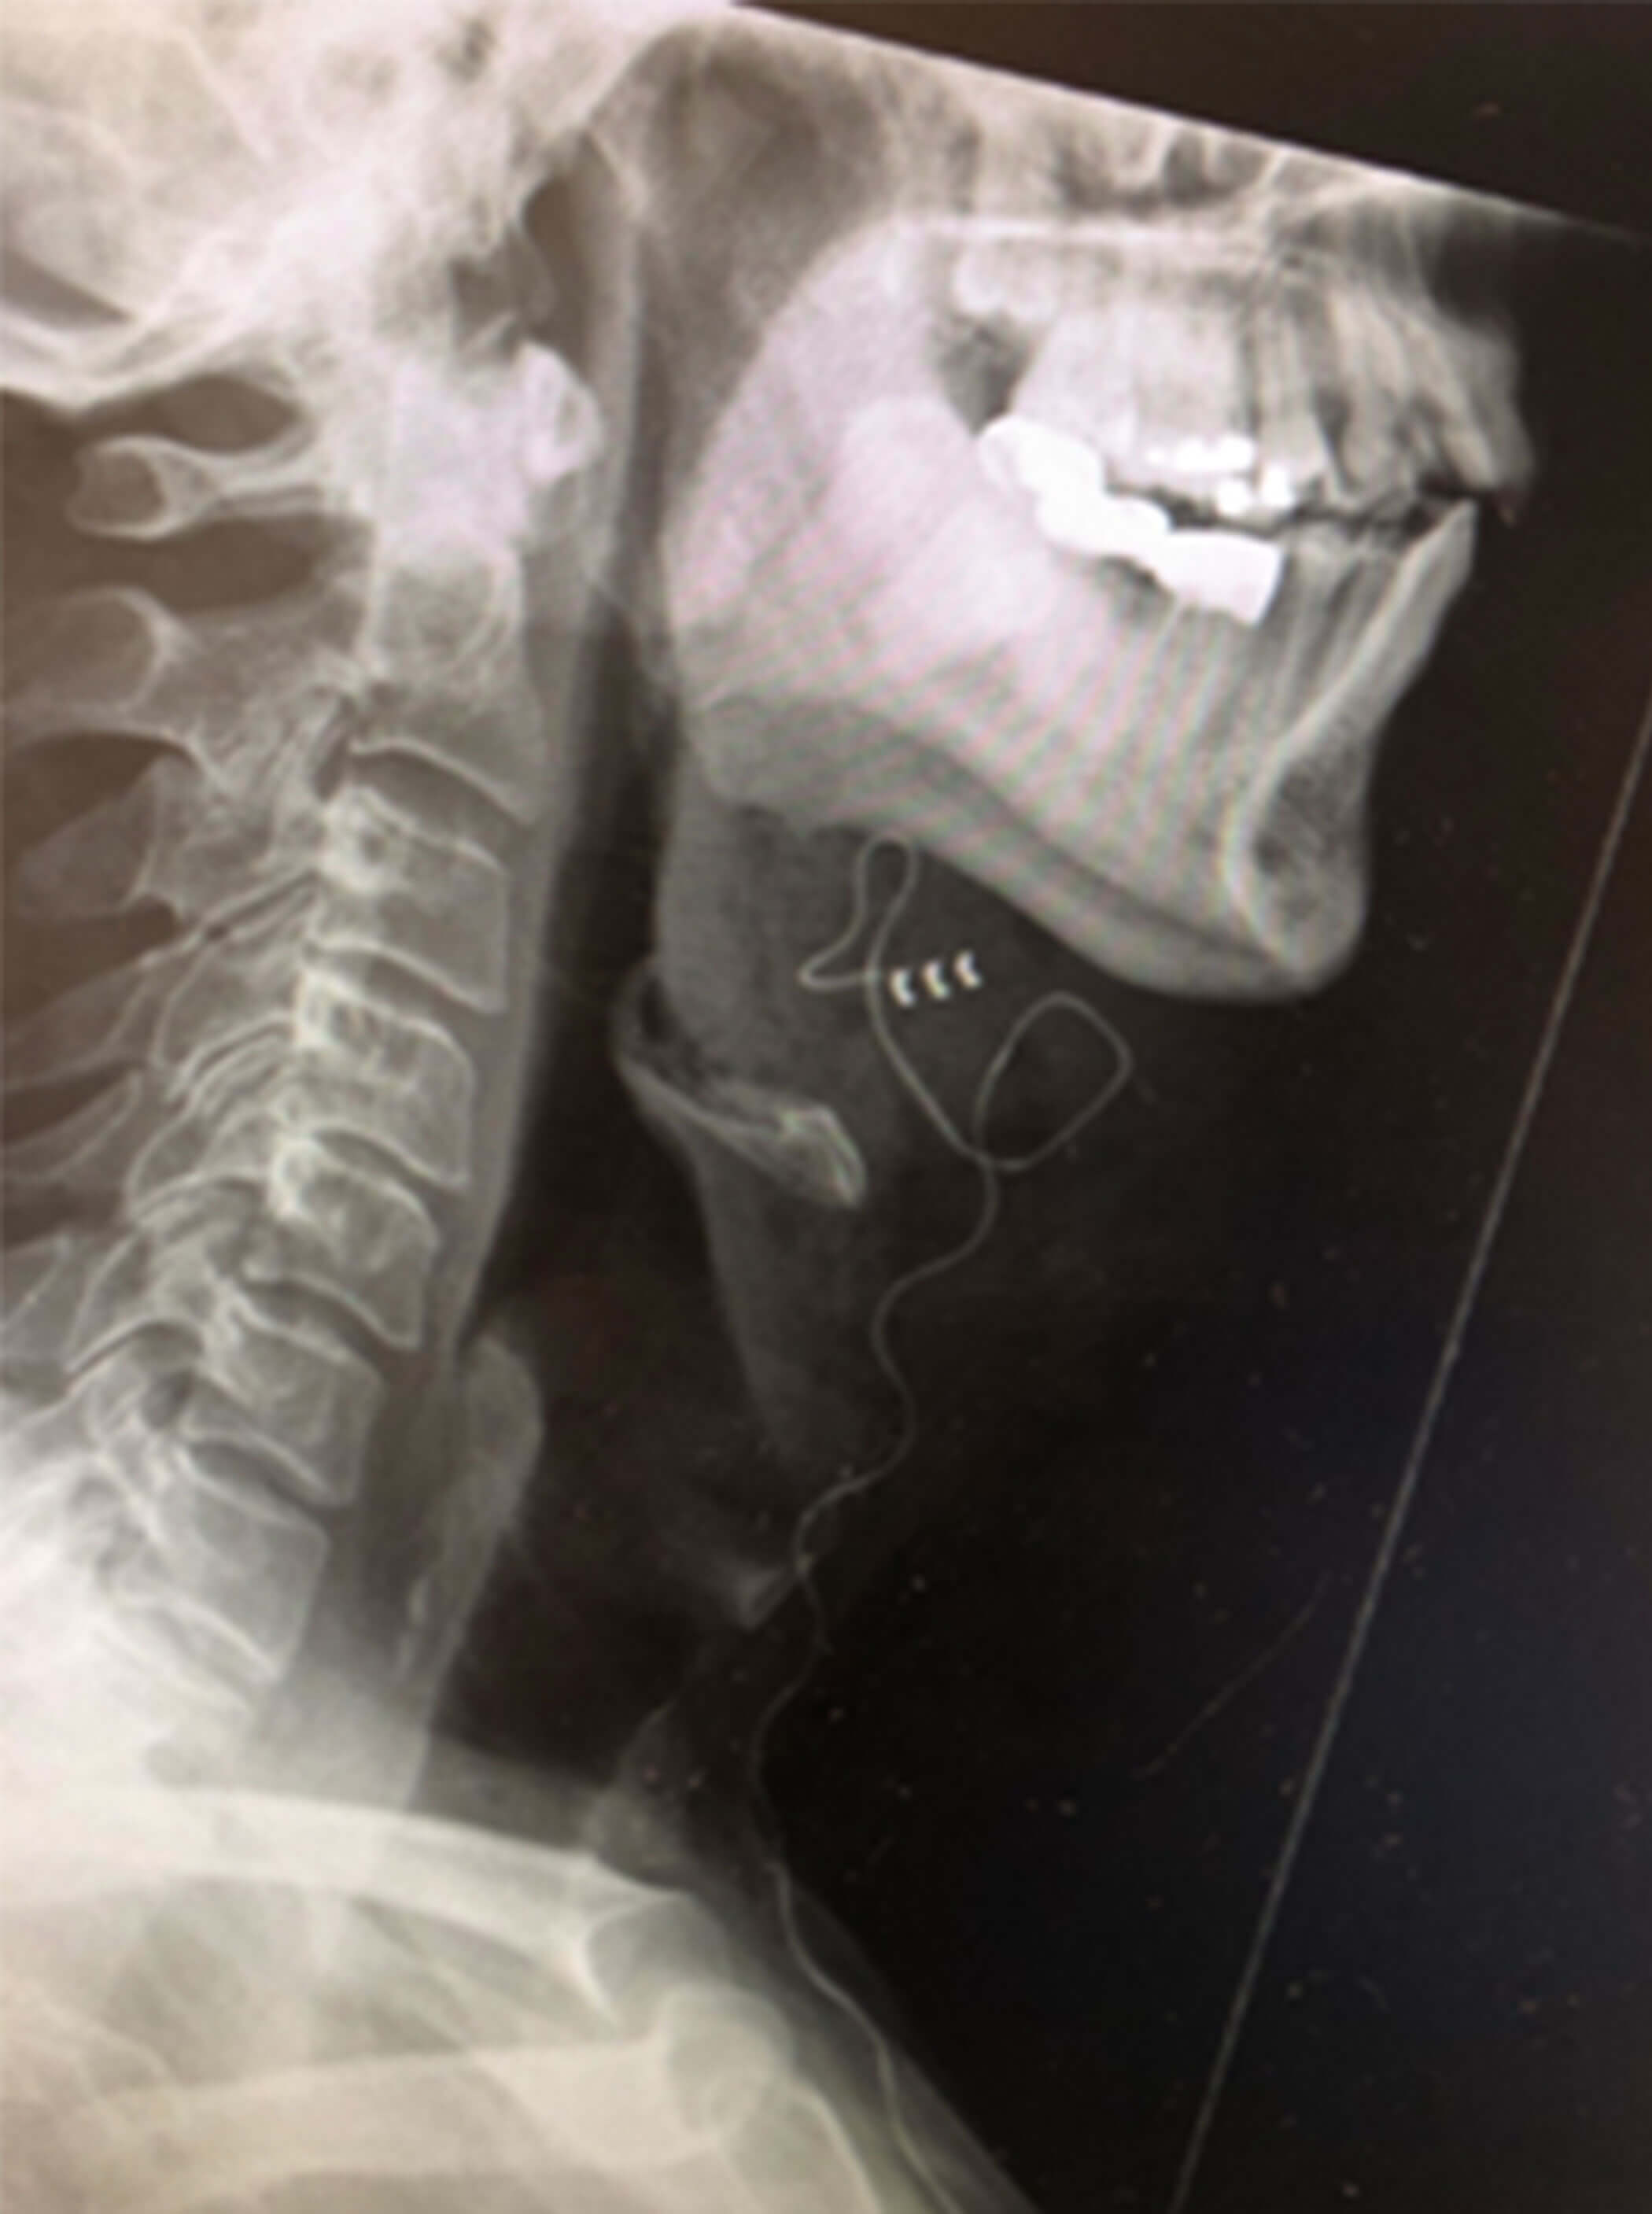

- An electrode cuff inserted on the branches of the hypoglossal nerve responsible for tongue protrusion (nerve supply to geniohyoid and genioglossus) through a 5cm incision on the right side of the neck, about 2cm below the inferior border of the right mandible (Figures 2a-d).

Figure 2a. Illustrating the neck incision on the right side,

about 2cm inferior to the lower border of the mandible.

Figure 2d. Postoperative right lateral neck X-Ray showing the electrode cuff

placed on the anterior branches of the hypoglossal nerve.